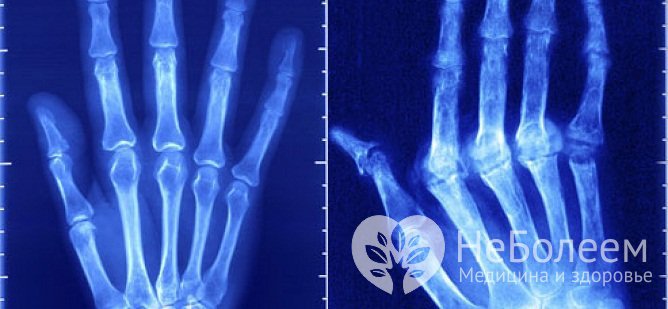

Стадии артритаКлиническая картина артрита пальцев рук отличается большой вариабельностью и зависит от этиологической формы и стадии болезни. Ранней стадии ревматоидного артрита свойственна скованность суставов по утрам и после длительного покоя. При этом возникает характерное ощущение тугих перчаток, ограничивающих подвижность кисти. В отдельных случаях у пациента может вовсе не быть жалоб, а единственными проявлениями заболевания служат ранние рентгенологические признаки артрита пальцев рук:

Характерные признаки воспаления суставов пальцев, как правило, наблюдаются на II стадии заболевания, начиная с появления болезненной припухлости, эритемы и крепитации в пораженных суставах, а к рентгенологическим признакам прибавляются множественные сужения межсуставных щелей, кистовидные просветления костной ткани и краевые деформации эпифизов костей. Вывихи, подвывихи и анкилозы суставов выявляют преимущественно на терминальных стадиях заболевания.

Артрит пальцев рук на рентгеновском снимкеЛабораторная диагностика играет решающую роль для установления причины воспалительной реакции. Общий анализ крови достоверно выявляет признаки воспалительного процесса. В ходе биохимического анализа крови определяется уровень мочевой и сиаловой кислоты, позволяющий подтвердить либо исключить диагноз подагрического артрита. Высокие показатели ревматоидного фактора и C-реактивного белка, фибриногена, серомукоида, криоглобулинов и т. д. указывают на ревматоидную патологию. В отдельных случаях показано лабораторное исследование пунктата синовиальной жидкости.